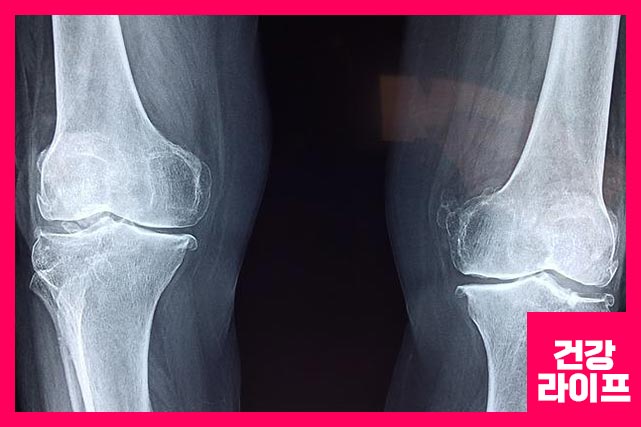

1. 골관절염

퇴행성 관절염이라고도 하는 골관절염이 있습니다. 무릎의 연골을 나이가 들면서 많이 사용하고 마모가 되면서 통증까지 생기게 합니다.